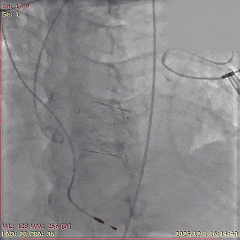

术中影像

初始造影确定无冠窦

瓣膜稳定释放至全展开

展开后造影,瓣膜位置可

多角度评估,确认瓣膜稳定

瓣膜脱钩后,无位移

最终造影,瓣膜位置可,无瓣周漏